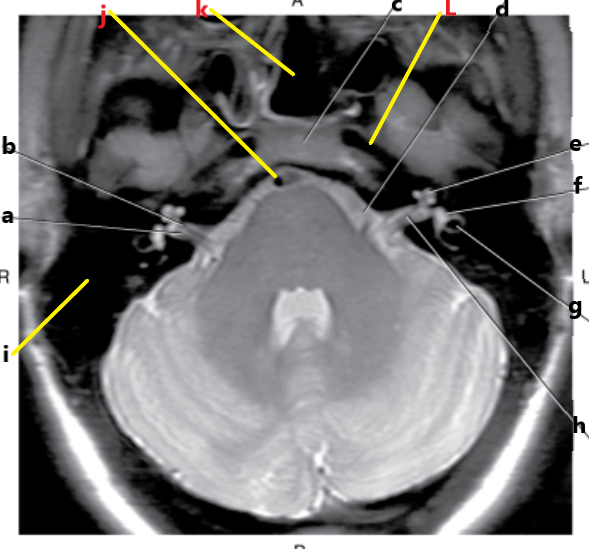

What is h ?

vestibulocochlear nerve

What is g ?

spinal cord

c and d are inside what structure ?

internal auditory canal

What is letter h ?

cerebral aqueduct